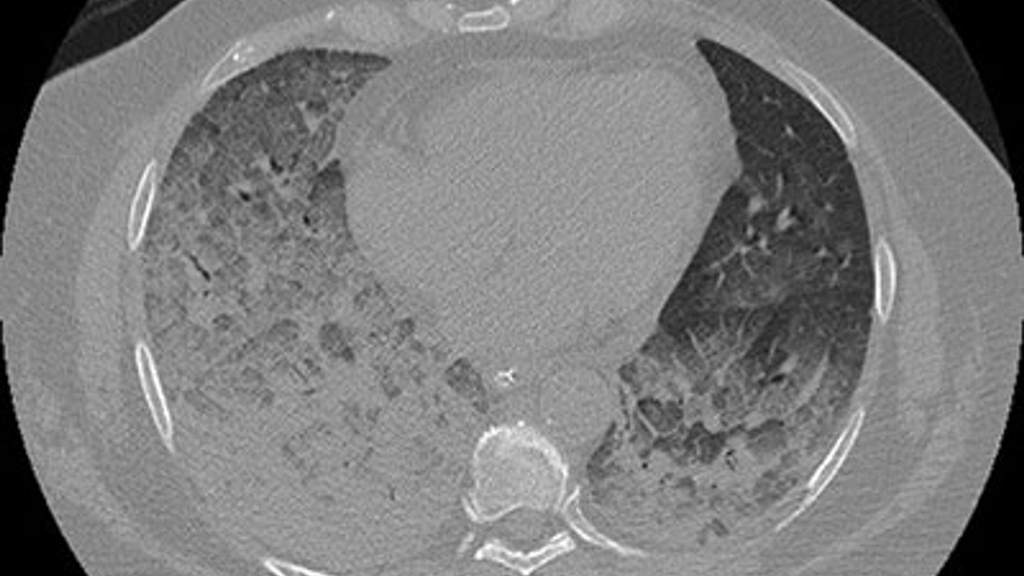

Chest CAT scan of a patient with active plastic bronchitis

Plastic bronchitis is usually diagnosed through a clinical exam along with imaging procedures such as a CAT scan and a study called Dynamic Contrast Enhanced Magnetic Resonance Lymphangiography (DCMRL).